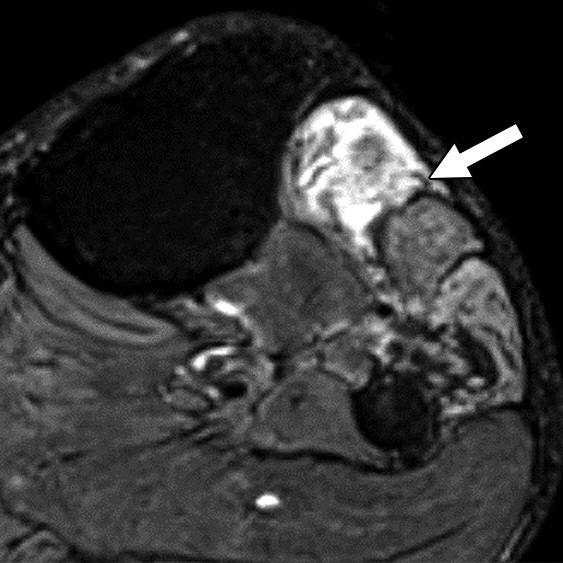

Axial (left) and oblique coronal (right) fat-suppressed T2-weighted images show proximally enlarged and hyperintense ulnar nerve (arrows) and normal nerve caliber distal to cubital tunnel (arrowhead on right).